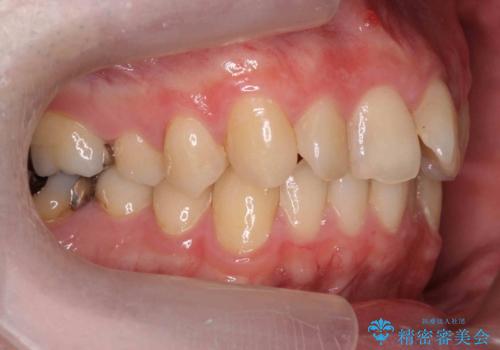

出っ歯と歯のねじれ 非抜歯で 30代男性

右の歯並びが1本分上が前にずれていました。

奥歯のかみ合わせを特に変えず、前歯の並びを整える治療をおこないました。

今回は右のかみ合わせはそのままにしました。左は特に初めから問題ない状態でした。